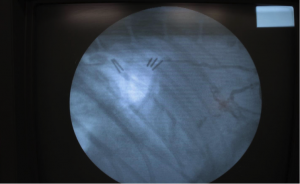

Cアームにて結紮前の胸管の走行を造影剤にて確認しているところです。

2箇所の結紮では胸管を完全に遮断することができませんでした。

2箇所の結紮では胸管を完全に遮断することができませんでした。画面左が頭側です。

さらに尾側に2本のチタンクリップで結紮することで胸管を完全に遮断できました。